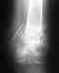

Евгений 22 года, г.Троицк Челябинской областиЗдравствуйте, доктор!Помогите пожалуйста узнать!!! Могут ли у вас провести операцию по первичному эндропротезированию тазобедренного сустава? платно или по федеральной квоте? Если платно, то какова будет сумма всей операции?Моей знакомой Авдошиной Алене (19 лет), попавшей 11 сентября 2009 года в страшную аварию требуется такая операция! Сама она из г.Балаково Саратовской области и родные не хотят ее оперировать в Саратове, врачам тем не доверяют! а О Вас я много хороших отзывов слышал от врачей нашего города! Помогите!!!!!!!!!!!!!!!!!!!!!!! Если необходимо я вышлю рентгенограммы и сканированные документы, только скажите какие!!!

Давайте начнем с более подробного описания проблемы и рентгенограмм.